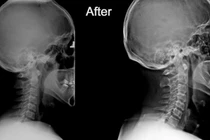

(khoahocdoisong.vn) - Mất đường cong sinh lý cổ gây tăng áp lực lên các đĩa đệm đốt sống cổ không chỉ gây thoái hóa hoặc thoát vị đĩa đệm mà còn giảm máu lưu thông lên não gây nhiều bệnh lý khó lường.